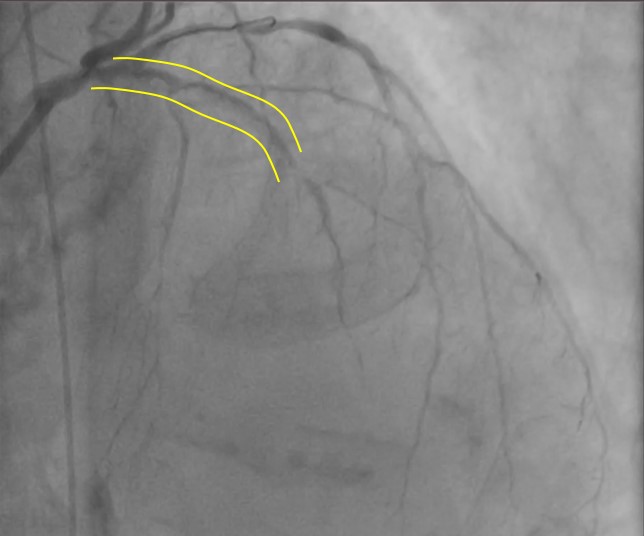

Coronaryangiography revealed diffuse calcified lesion in the LM at bifurcation with 70%stenosis, 99% stenosis at proximal LAD, and 99% stenosis at mid-LAD. Thepatient was diagnosed as CAD, UAP, Heart failure class II NYHA.

Through radial artery access, guiding catheter 1 (7F/EBU3.75) was inserted into the distal LAD. Guidewire 1 (Asahi Sion Blue) and guidewire 2 (Abbott) was unable to reach distal LAD segment and the distal D segment. Balloon 1 (1.0x10 mm, 8 atm) could not pass proximal LAD when sent along the guidewire 1. IVUS of the LAD-LM showed diffuse calcification with >2700 circular arc. Rotational atherectomy was targeted to distal LAD. High-speed rotational atherectomy and low-speed plaque modification was performed on proximal-mid LAD lesions. Then, guidewire 1 (Asahi Sion Blue) was advance to distal LAD. IVUS on LAD-LM revealed circumferential calcification. Intravascular shockwave energy was used to inflate the balloon (3.0 x 12 mm shockwave balloon) at 4-6 atm and then IVUS showed a rupture of deep LAD calcified ring. Then, the distal LAD was predilated [Balloon 2 (1.5x20 mm, 6-12 atm), balloon 3 (2.0x20mm, 6-12 atm), balloon 4 (2.0x20 mm, 6-12 atm) and balloon 5 (NC balloon 2.0x20 mm, 20 atm)]. Stent 1 (DES 2.25x23 mm, 9 atm), stent 2 (DES 2.75x30 mm, 9 atm), stent 3 (DES 3.00x30 mm, 9 atm), stent 4 (DES 3.50x 28mm, 9 atm) was planted on the mid LM-LAD segment and then balloon 6-10 (PTCA ballon 2.75 x12mm, 14-28 atm); (PTCA ballon 3.00x 12mm, 14-28 atm); (PTCA ballon 3.00x15 mm, 14-28 atm); (NC balloon 3.00 mm x 15 mm, 14-28 atm); (coronary mastoid 3.00x15 mm , 14-28 atm) was planted for post dillatation. Post procedural IVUS showed satisfactory result.